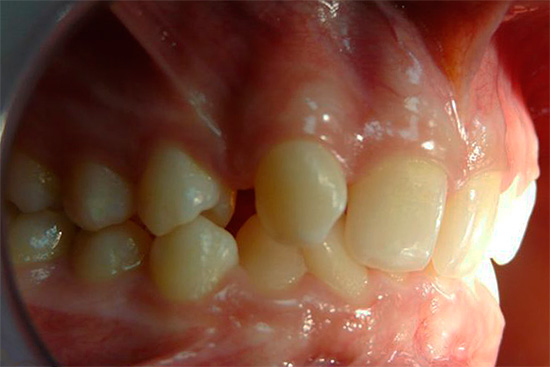

La fotografia sotto mostra un esempio di morso incrociato in un adulto:

Reclami frequenti da pazienti e genitori:

- la presenza di un difetto estetico con una notevole discrepanza tra dimensione e posizione delle mascelle;

- difficoltà a mangiare;

- violazione della pronuncia del suono;

- malattia gengivale dovuta a possibili lesioni durante la masticazione e la parola;

- problemi al tratto gastrointestinale.